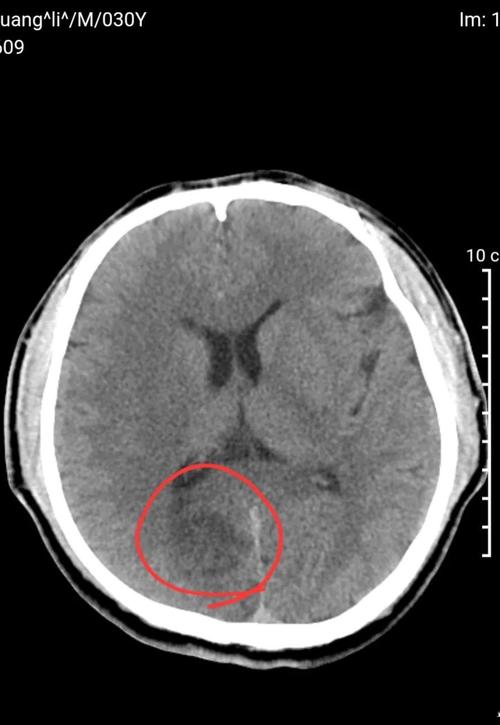

后期梗死灶形成: 当脑缺血持续超过6-12小时后,缺血中心的脑细胞开始坏死、水肿,这时在CT上会表现为低密度灶(颜色比周围正常的脑组织要暗),这个区域就是坏死的脑组织。

(图片来源网络,侵删)